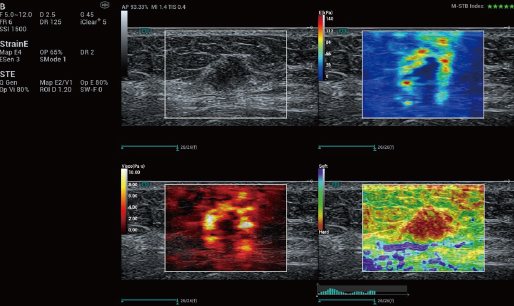

STVi maakt de kwantitatieve evaluatie van weefselviscositeit mogelijk en biedt realtime, multi-parametrische beeldvorming. Dit maakt een bredere benadering mogelijk van beeldvormingsdiagnose en kwantitatieve analyse van chronische leverziekten, borstlaesies en andere aandoeningen.

Meerdere kwantificeringstools

Beoordeling van borsttumoren